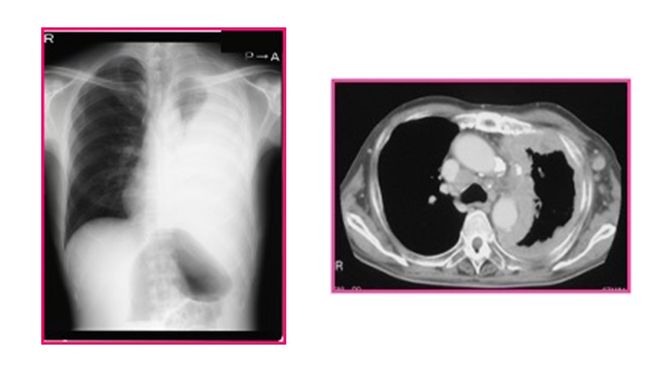

2024年4月,她去仙台市医院检查,一张弥漫性恶性胸膜间皮瘤的诊断书给她的人生画上了句号。

医生明确表示,这种病的主要诱发因素是石棉,而A子接触石棉的源头大概就是当年工作中天天打交道的粉底和爽身粉。

目前日本针对弥漫性恶性胸膜间皮瘤的治疗手段主要是手术、化疗和靶向治疗,虽然纳入了医保,但治疗过程十分痛苦。